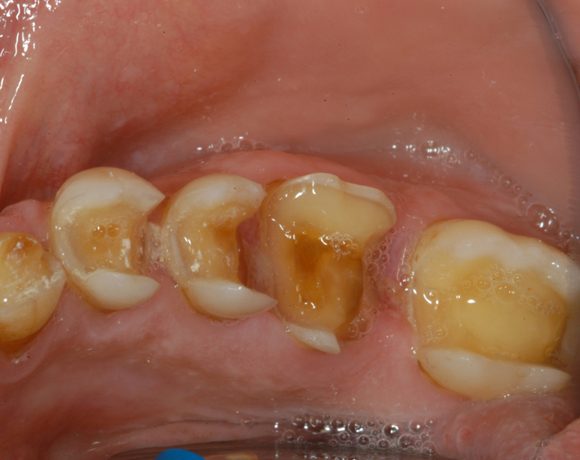

Im vorliegenden Patientenfall waren die Zähne 11 – 26 mit einer provisorischen Brücke versorgt, der Patient konnte damit aber nicht essen. Auch im Unterkiefer waren die vorhandenen Kronen und Brücken insuffizient. Es wurde eine komplette Neuversorgung für Ober- wie Unterkiefer geplant.